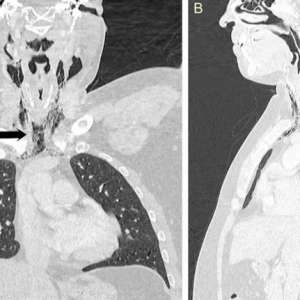

Мужчина столкнулся с разрывом горла, когда попытался подавить чих.

В попытке сдержать чих он почувствовал «хлопок» в шее, за которым последовали боль и трудности при глотании. МРТ показало, что воздух выходил через разрыв из трахеи в мягкие ткани шеи. В течение следующих нескольких дней мужчину кормили через зонд, чтобы дать тканям время для заживления.

Когда мы прикрываем нос и рот во время чихания, воздуху некуда деваться, и его давление разрывает мягкие ткани, нанося им вред.